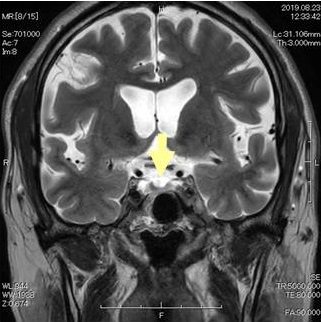

エンプティ・セラ症候群(empty sella症候群, トルコ鞍空洞症候群)は、クモ膜下腔がトルコ鞍内に下垂し、脳脊髄液で満たされた状態。原因は原発性、妊娠、自己免疫性下垂体炎、下垂体卒中、下垂体手術や放射線療法後。症状は視力障害、頭痛、脳脊髄液漏、下垂体機能低下症、中枢性甲状腺機能低下症[視床下部性(3次性)甲状腺機能低下症]、視床下部機能障害、高プロラクチン血症、先端巨大症、クッシング病、SITSH(TSH不適切分泌症候群)を引き起こす事も。原発性甲状腺機能低下症(橋本病・非橋本病)合併が多い。ダイナミックMRIで診断。治療は一般的に外科手術適応外。

エンプティ・セラ症候群(empty sella症候群, トルコ鞍空洞症候群)は、クモ膜下腔がトルコ鞍内に下垂し、トルコ鞍が脳脊髄液で満たされた状態です。

鞍隔膜の形成不全→トルコ鞍で髄液の拍動を強く受ける→くも膜下腔が下垂→下垂体が菲薄化